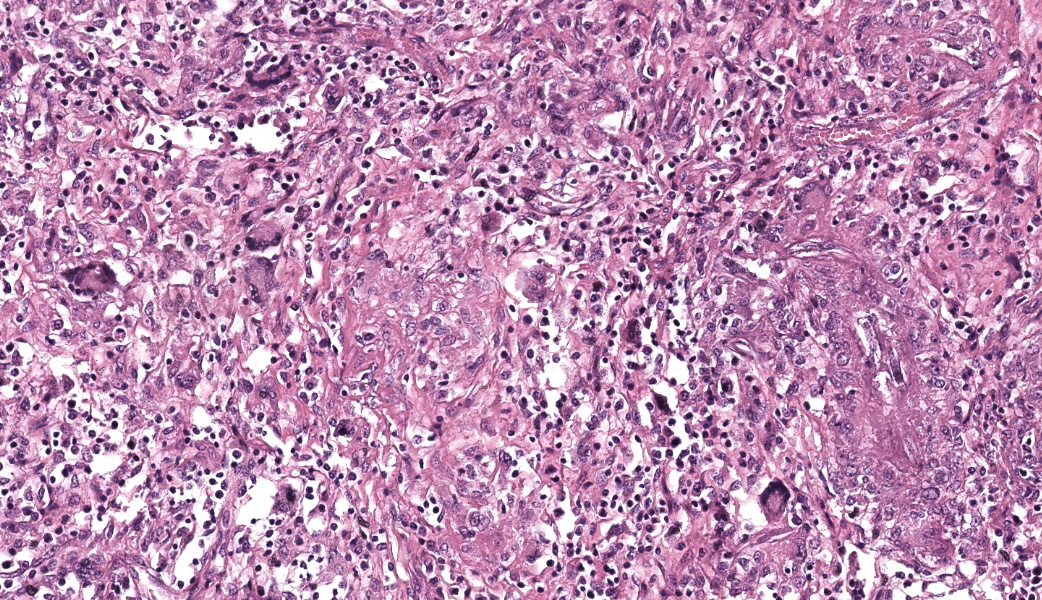

Microscopic Description:

Kidneys: Multifocal to coalescent areas of loss of normal parenchyma with replacement by severe lymphohistioplasmocytic inflammatory infiltrate, with epithelioid macrophages, multinucleated giant cells, and large numbers of intralesional nematodes. Parasites were elongated, with aproximately 80 to 90 μm long (most of them fragmented), cylindrical, with sharp ends, covered by smooth cuticle, platimiarian musculature and an evident elongated and central rhabditiform esophagus, occupying the initial third of the body (morphology consistent with Halicephalobus gingivalis). Associated with these lesions there were also fibroplasia, necrosis, vasculitis and the remaining renal tubules were dilated and filled with macrophages, neutrophils, cellular debris, and numerous sections of H. gingivalis.

Contributor’s Morphologic Diagnoses:

Kidneys: multifocal to coalescent, severe, chronic, granulomatous nephritis associated to intralesional nematodes compatible with Halicephalobus gingivalis and multifocal, severe, vasculitis, horse.

Kidney: Nephritis, granulomatous, chronic-active, multifocal to coalescing, severe, with adult and larval rhabditid nematodes and eggs.